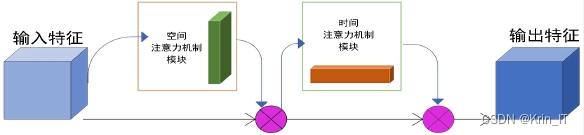

针对这一挑战,提出了一种时空注意力机制,旨在借鉴卷积注意力机制的有效性,以提高肺结节的追踪能力。通过结合时间和空间的特征信息,时空注意力机制能够在多张CT图像中聚焦于与肺结节相关的关键区域,增强对重要特征的关注。这种机制不仅能够提高对肺结节的检测准确性,还能减少由于角度变化引起的误诊概率,为临床提供更为可靠的辅助诊断工具。通过这种创新的时空注意力机制,肺结节检测在复杂的动态CT图像中将变得更加高效和精准。

在检测到疑似肺结节的位置后,将为每个结节分配一个卷积神经网络(CNN)分支进行跟踪。这意味着,若存在多个肺结节,则会相应地创建多个CNN分支,以便对每个结节进行独立跟踪。同时,时间注意力机制在参数更新过程中体现了每一帧的预测跟踪框对损失函数的权重贡献,从而优化模型的学习过程。α参数则是需要学习的权重,能够有效调整不同特征图对最终预测的影响。

在主干网络的改进方面,原版YOLOv5的主干网络部分大体保留了YOLOv4的结构,但CSPDarknet53由于参数量庞大,对计算机的存储和计算能力要求较高,进而影响了运行速度。为了解决这一问题,研究参考了Ghost bottleneck结构,对其进行了改进。新的Ghost bottleneck结构中引入了前述的时空注意力机制,尽管增加了部分参数,但这一机制是为了适应肺部CT影像中可能出现的多种肺结节而专门设计的,从而能够更准确地提取特征信息。尽管整体计算量有所增加,但相较于YOLOv5原有的CSPDarknet53结构,其计算复杂度仍然显著降低。改进后的Ghost bottleneck结构(简称G-BNeck)通过增强特征提取能力,进一步提升了模型在复杂任务中的表现。

以YOLOv5的主体结构为基础,首先将骨干网络部分更改为改进的Ghost bottleneck(G-Bneck)结构,这一改动使得网络更加轻量化,提升了运行效率。随后,在G-Bneck中引入了时空注意力机制,以减少冗余信息对识别效果的影响,增强了模型对关键特征的关注能力。结合SPP结构与FPN(特征金字塔网络)和PAN(路径聚合网络),构建了一个特征深度融合提取网络,实现对目标特征的详尽提取。最终,通过这一改进的网络结构输出预测结果,完成了算法的构建任务。